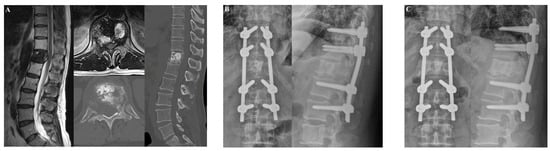

3.1.2. Case 2